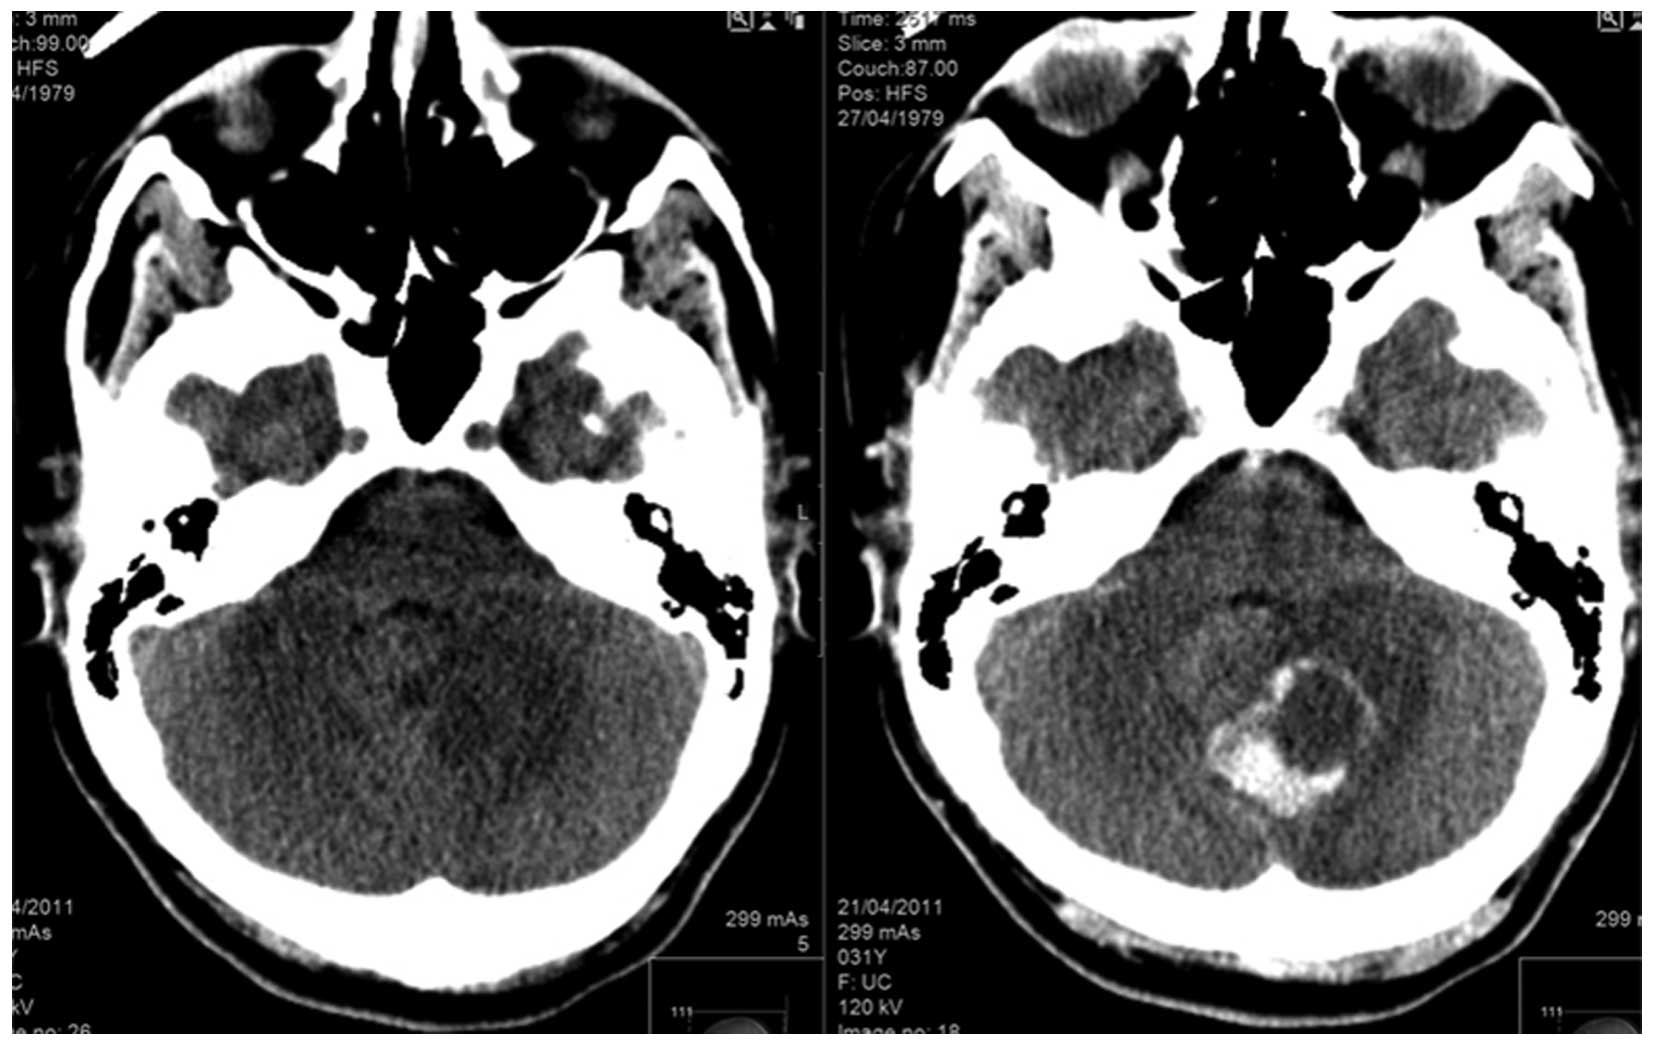

The patient was lost to follow-up until April 2011 when she was admitted The Emek Medical Center due to severe headaches and blurred vision. Brain magnetic resonance imaging (MR750w 3.0T; GE Healthcare, Milwaukee, WI, USA) demonstrated the presence of a posterior brain tumor (Fig. 1). Posterior craniotomy and resection of the tumor was performed. The pathological report diagnosed the tumor as metastatic PEComa identical to the small bowel origin (Fig. 2).